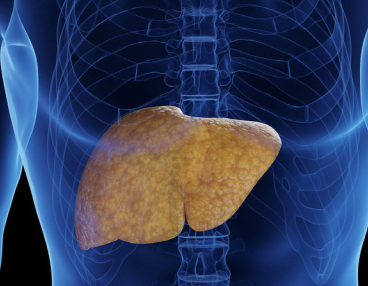

술 안마셔도 생기는 비알코올성 지방간, 원인은?

지방간은 이름 그대로 간에 지방이 많이 낀 상태를 말한다. 간 무게의 5% 이상이 지방으로 쌓이게 되면 지방간으로 진단한다. 그 중 비알코올성 지방간은 하루에 40g(4잔) 이하의 음주를 하는 사람에게 생기는 지방간을 말한다. 이는 대부분 과체중, 비만(복부 비만), 당뇨병, 고지혈증 등의 위험 요인과 관련이 있다.

10명 중 최소 2명은 '비알코올성 지방간'

중년 남성 중 비알코올성 지방간 없는 사람은 찾아보기 힘들다고 할 만큼 비알코올성 지방간은 흔한 질환이다. 비알코올성 지방간은 하루에 40g(4잔) 이하의 음주를 하는 사람에게 생기는 지방간을 말한다. 지방간 그 자체로는 대부분 증상이 없다보니 심각성을 느끼지 못하지만, 증상이 없어도 놔두면 다른 중증 질환으로 발전하기 쉬우므로 관리가 필요하다. 지방간이 심해질수록 간암 17배, 대장암 2배, 관상동맥질환은 4배 발생 위험성이 높아진다.